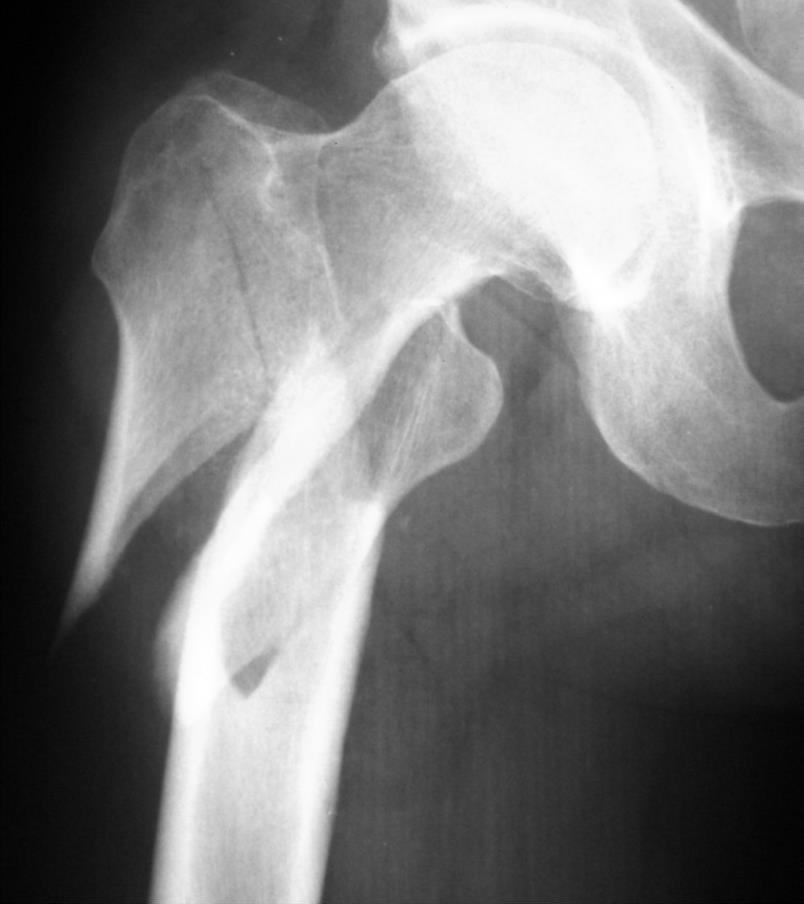

To złamanie według klasyfikacji AO powinno być oznaczone symbolem:

Pytanie 76